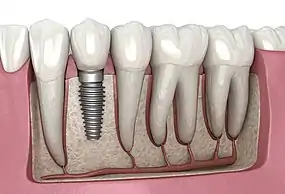

A titanium dental implant with a crown attached used for a single tooth replacement

Dental Implant, 3D Illustration

A dental implant (also known as an endosseous implant or fixture) is a prosthesis that interfaces with the bone of the jaw or skull to support a dental prosthesis such as a crown, bridge, denture, or facial prosthesis or to act as an orthodontic anchor. The basis for modern dental implants is a biological process called osseointegration, in which materials such as titanium or zirconia form an intimate bond to the bone.[1] The implant fixture is first placed so that it is likely to osseointegrate, then a dental prosthetic is added. A variable amount of healing time is required for osseointegration before either the dental prosthetic (a tooth, bridge, or denture) is attached to the implant or an abutment is placed which will hold a dental prosthetic/crown.